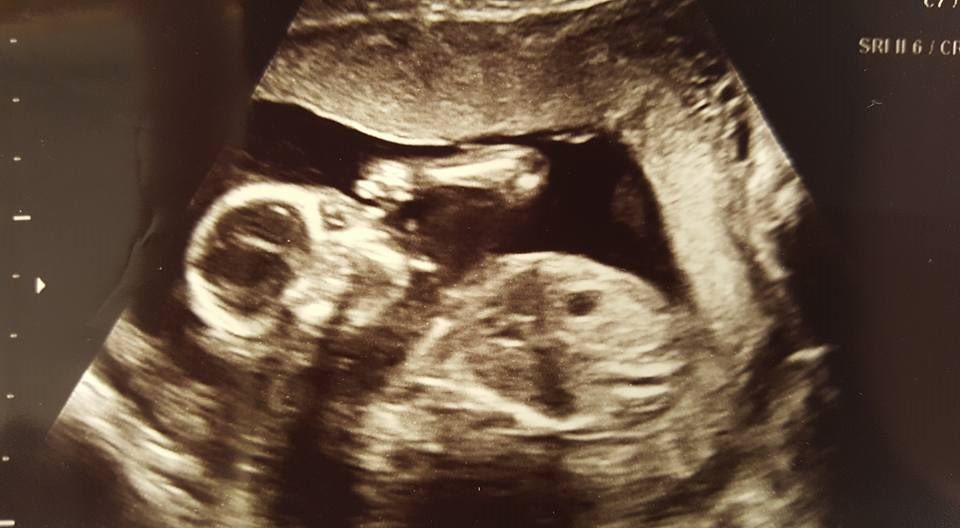

I started a routine of having ultrasounds every 4 weeks throughout the entire pregnancy (most women have 2 ultrasounds during their pregnancy, one in the 1st trimester to confirm implantation and one around 20 weeks for anatomy scan). I also had a full work up to see if there was a reason for my past miscarriages (they did not find anything). I was very sick with dehydration, non-stop nausea and vomiting, weight loss, etc. until around 14 weeks. I continued to cramp and bleed until around 20 weeks. Every ultrasound I had showed a healthy and growing baby even though my body was not tolerating being pregnant very well.

Had I terminated with the initial hospital visit, I would not have my perfect son, Kaleb, today.